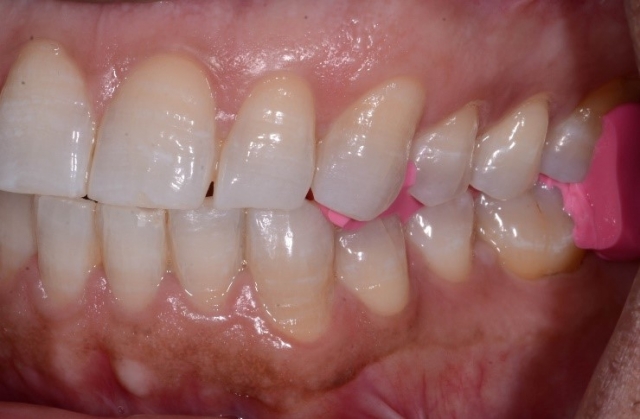

Scanning the upper and lower arch and taking digital impressions. Call it what you want. I call it not taking an alginate or PVS impression (Fig. 1).

Cheating? Slacking? Taking shortcuts? I guess, if that’s the way you feel. I don’t. I call it brilliant if it’s at least as accurate, faster, and easier for the patient. And so it is. Evaluate it, critique it, research it, try it. No need to overthink it, right?